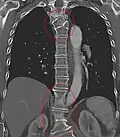

Als Blockwirbel wird die teilweise oder ganze Verschmelzung (Fusion) zweier oder mehrerer Wirbelkörper bezeichnet. Die Verschmelzung kann durch eine Entwicklungsstörung bedingt (dysontogenetischer Blockwirbel) oder im Laufe des Lebens erworben sein.

Eine dysontogenetische Blockwirbelbildung findet sich zum Beispiel beim Klippel-Feil-Syndrom.

Erworbene Blockwirbel können sich z. B. nach Entzündungen der Wirbel und Bandscheiben (z. B. nach Tuberkulose), nach Trauma oder bei ausgeprägter Degeneration der Bandscheiben und angrenzenden Wirbel (Osteochondrosis intervertebralis) ausbilden.